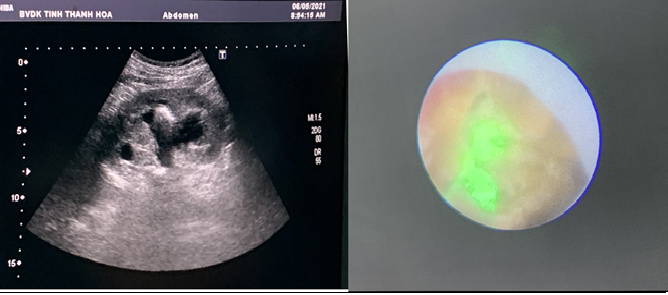

Thì 2: BN ở tư thế nghiêng P 90o, tiến hành chọc dò vào bể thận đài giữa quan sát siêu âm, tiếp cận sỏi qua bể thận và tán vụn sỏi bằng năng lượng laser, lấy sỏi vụn qua amplatz, sau mổ đặt dẫn lưu thận T bằng sonde Mono J size 14Fr

Hình 2 Hình ảnh siêu âm và sỏi trong quá trình phẫu thuật